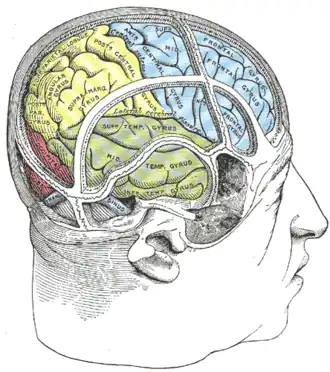

Drawing to illustrate the relations of the brain to the skull.

Drawing to illustrate the relations of the brain to the skull. -